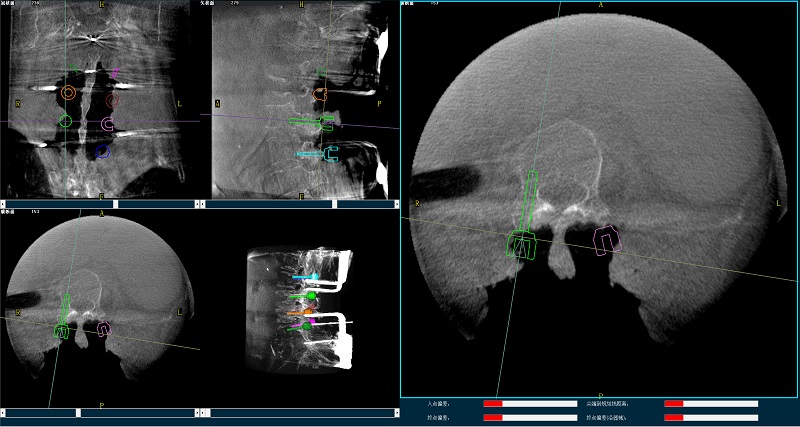

三维图像

(2)使用普爱医疗平板三维C形臂扫描患者,得到术中三维图像并传送至骨科机器人导航系统。骨科机器人导航系统基于高清术中三维图像进行手术规划。

手术规划图像

(4)在骨科机器人导航系统辅助下,一次性准确植入8枚椎弓根螺钉。